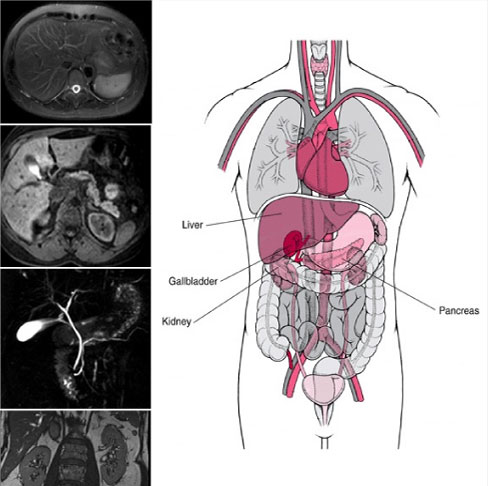

Abdominal Imaging

Abdominal magnetic resonance imaging (MRI) is a noninvasive procedure that uses powerful magnets and radio waves to produce pictures of the inside of the abdomen without exposure to ionizing radiation (x-rays).

Abdominal Magnetic Services

• Conventional Abdomen- Pelvis Imaging

• MRCP

• Liver Imaging (Triphasic Scan)

• MR Defecography

• MR Enterography

• MR Urography

• Renal Angiography

• MP MRI for Prostate

• Male/Female Pelvic MRI

• Abdominal Aortogram